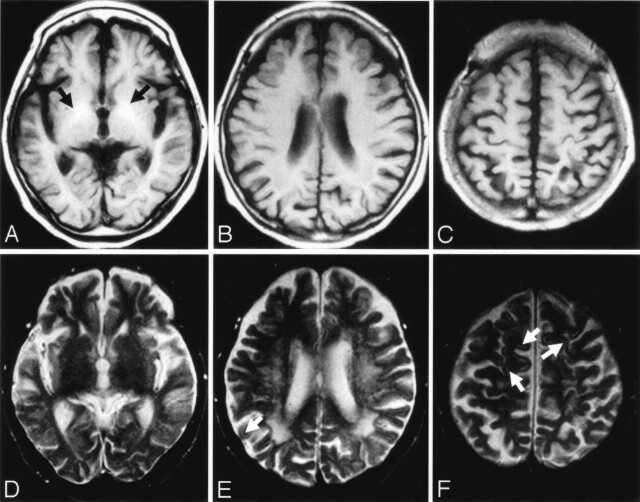

Fig 1.

Case 1.

A–C, Axial T1-weighted MR images obtained 2 days after admission. T1-weighted image (A) shows hyperintensities in the globus pallidus on both sides (arrows). T1-weighted images show no definite signal intensity changes in the cerebral cortices (A–C).

D–F, T2-weighted MR images obtained 2 days after admission. Signal intensity abnormalities are difficult to discern on T2-weighted image (D). T2-weighted images (E and F) show focal, faint hyperintensities in the cerebral cortices (arrows). Confluent and diffuse T2 hyperintensities are seen in the deep and subcortical cerebral white matters (E).